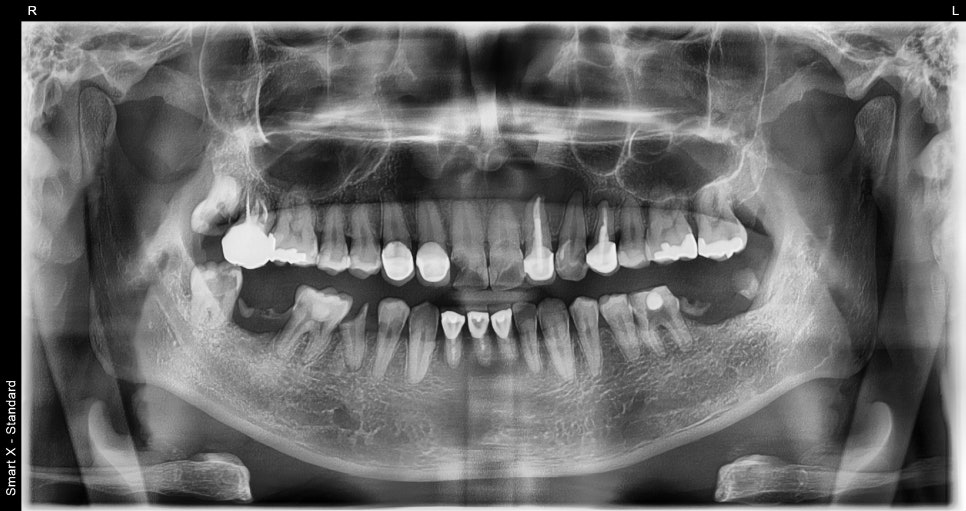

but to make an accurate diagnosis, we performed panoramic X-ray and CT imaging.

When we examined the inside of the front tooth that seemed to have only a simple fracture,

a large cyst (periapical cyst) had formed in the root area of tooth #11,

and overall, there was extensive tooth damage requiring treatment.

📸 Before surgery

– Cystic lesion in the periapical area